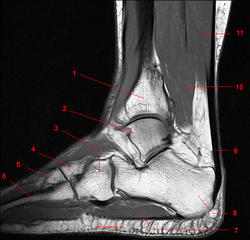

Рис. 16

1, Длинный разгибатель пальцев. 2, Малоберцовая кость. 3, Сухожилие длинной малоберцовой мышцы. 4, Сухожилие короткай малоберцовой мышцы. 5, Пятая плюсневая кость. 6, Мышца, отводящая мизинец стопы. 7, Длинная малоберцовая мышца.